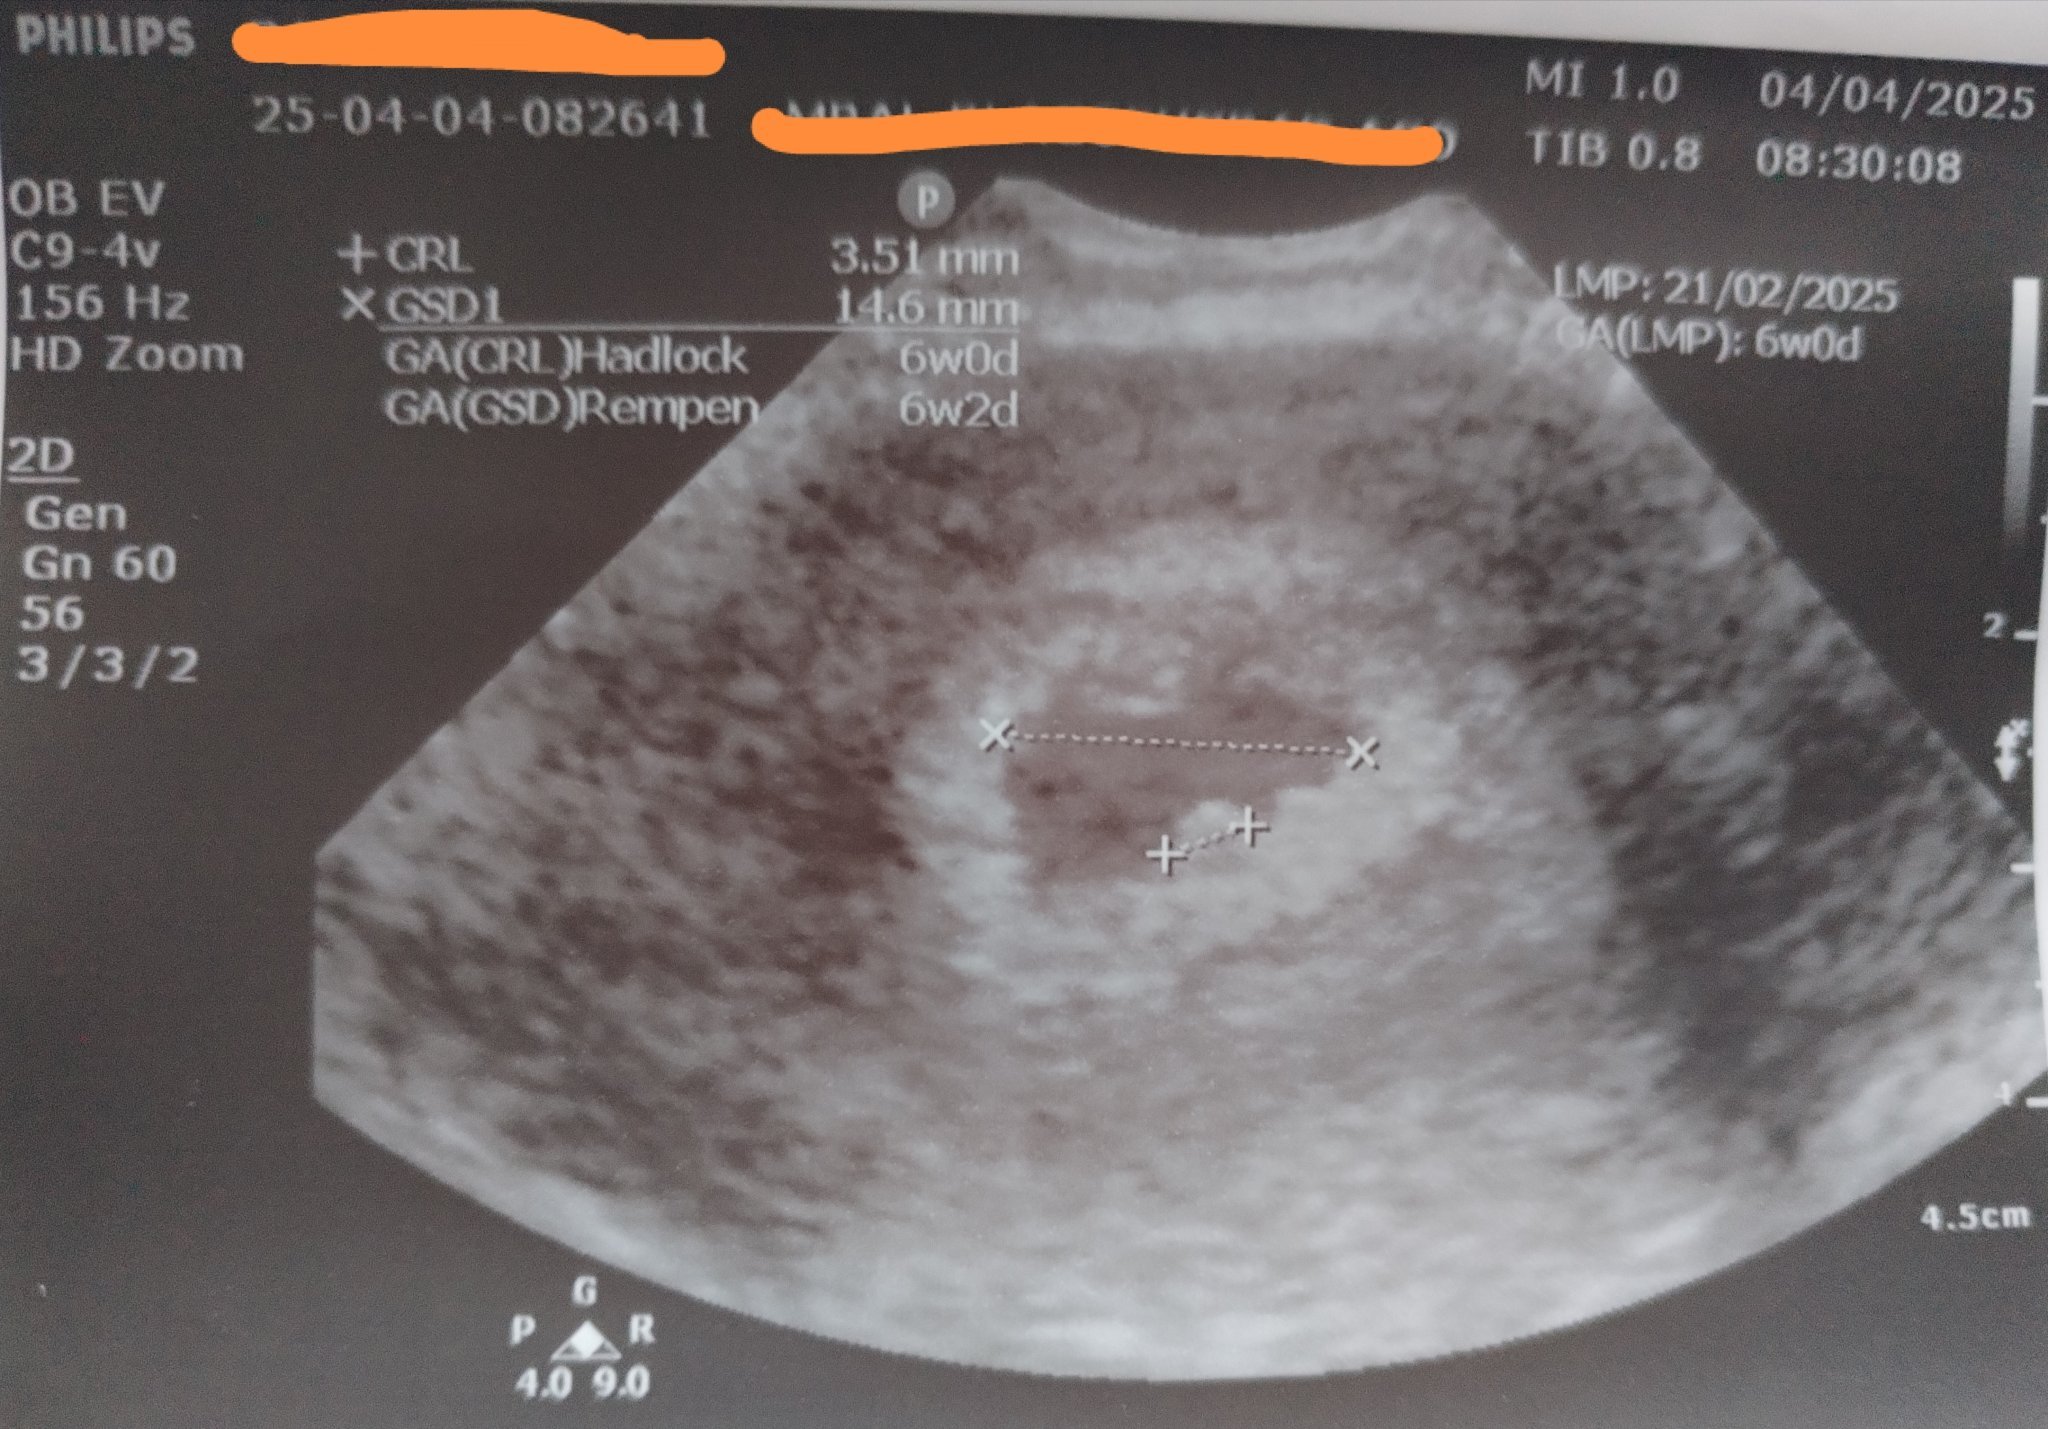

Здравейте! Може ли някой да ми каже дали всичко е наред? На първата снимка се видя, че бременността е маточна и каза, че всичко е наред, на втората снимка в 6 седмица все още не се чува пулс, каза, че плодния сак е пораснал и отговаря на седмиците си но каза нещо ембрионално не е пораснало. Не можах да разбера какво иска да каже с това, моля някой да ми помогне